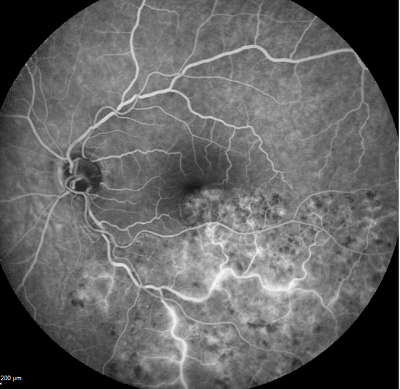

angiographie